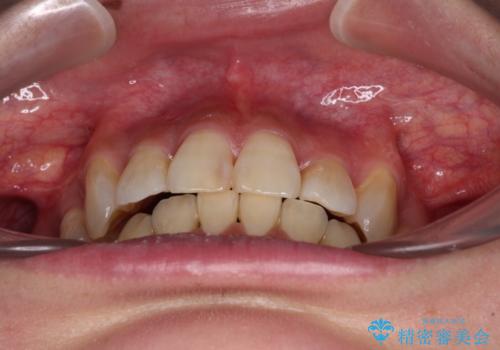

- 八重歯や前歯のデコボコを気にして来院された患者様です。

目立たない装置を希望されたので、上顎が裏側装置のハーフリンガルを選択し、上下左右の小臼歯(計4歯)を抜歯して矯正治療を行うこととしました。

補助装置を併用することで、八重歯を速やかに改善し、治療期間の短縮を図ることとしました。